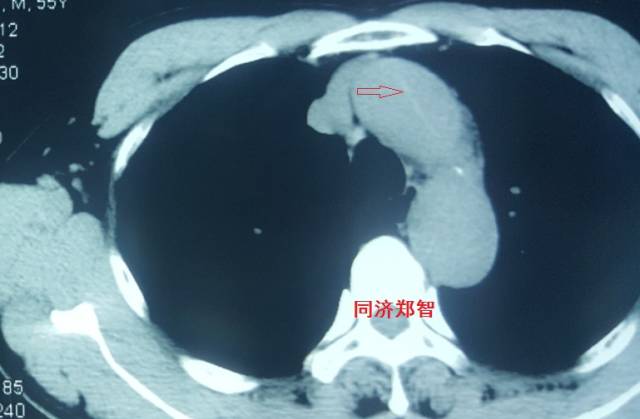

病例一

胸片提示左上纵隔影增宽(红色星形标记),CTA证实B型主动脉夹层伴降主动脉夹层动脉瘤形成。